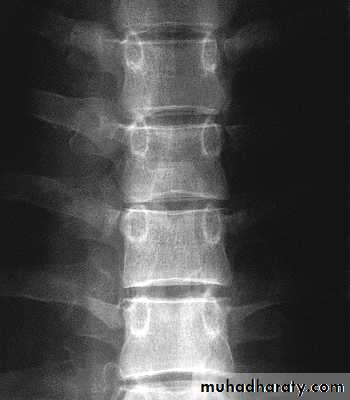

Lumbar Spine X Ray

Lateral radiograph

A/P radiograph• Sacrum